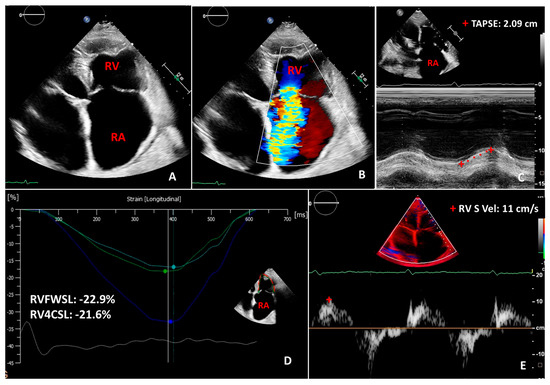

- Rudski, L.G.; Lai, W.W.; Afilalo, J.; Hua, L.; Handschumacher, M.D.; Chandrasekaran, K.; Solomon, S.D.; Louie, E.K.; Schiller, N.B. Guidelines for the echocardiographic assessment of the right heart in adults: A report from the American Society of Echocardiography endorsed by the European Association of Echocardiography, a registered branch of the European Society of Cardiology, and the Canadian Society of Echocardiography. J. Am. Soc. Echocardiogr. 2010, 23, 685–713. [Google Scholar] [CrossRef]

- Lee, J.Z.; Low, S.W.; Pasha, A.K.; Howe, C.L.; Lee, K.S.; Suryanarayana, P.G. Comparison of tricuspid annular plane systolic excursion with fractional area change for the evaluation of right ventricular systolic function: A meta-analysis. Open Heart 2018, 5, e000667. [Google Scholar] [CrossRef] [PubMed]

- Haeck, M.L.; Scherptong, R.W.; Marsan, N.A.; Holman, E.R.; Schalij, M.J.; Bax, J.J.; Vliegen, H.W.; Delgado, V. Prognostic value of right ventricular longitudinal peak systolic strain in patients with pulmonary hypertension. Circ. Cardiovasc. Imaging 2012, 5, 628–636. [Google Scholar] [CrossRef] [PubMed]

- Sachdev, A.; Villarraga, H.R.; Frantz, R.P.; McGoon, M.D.; Hsiao, J.F.; Maalouf, J.F.; Ammash, N.M.; McCully, R.B.; Miller, F.A.; Pellikka, P.A.; et al. Right ventricular strain for prediction of survival in patients with pulmonary arterial hypertension. Chest 2011, 139, 1299–1309. [Google Scholar] [CrossRef] [PubMed]

- Carluccio, E.; Biagioli, P.; Alunni, G.; Murrone, A.; Zuchi, C.; Coiro, S.; Riccini, C.; Mengoni, A.; D’Antonio, A.; Ambrosio, G. Prognostic Value of Right Ventricular Dysfunction in Heart Failure with Reduced Ejection Fraction: Superiority of Longitudinal Strain Over Tricuspid Annular Plane Systolic Excursion. Circ. Cardiovasc. Imaging 2018, 11, e006894. [Google Scholar] [CrossRef] [PubMed]

- Bannehr, M.; Kahn, U.; Liebchen, J.; Okamoto, M.; Hähnel, V.; Georgi, C.; Dworok, V.; Edlinger, C.; Lichtenauer, M.; Kücken, T.; et al. Right Ventricular Longitudinal Strain Predicts Survival in Patients with Functional Tricuspid Regurgitation. Can. J. Cardiol. 2021, 37, 1086–1093. [Google Scholar] [CrossRef] [PubMed]

- Ancona, F.; Melillo, F.; Calvo, F.; Attalla El Halabieh, N.; Stella, S.; Capogrosso, C.; Ingallina, G.; Tafciu, E.; Pascaretta, A.; Ancona, M.B.; et al. Right ventricular systolic function in severe tricuspid regurgitation: Prognostic relevance of longitudinal strain. Eur. Heart J.-Cardiovasc. Imaging 2021, 22, 868–875. [Google Scholar] [CrossRef] [PubMed]